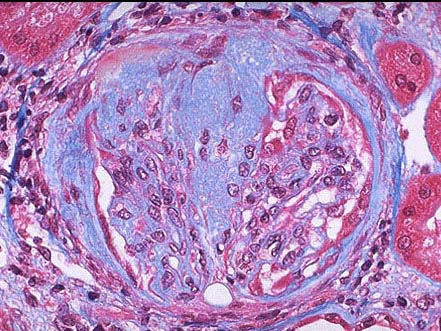

患者女性,25岁,周身高度水肿伴腹水。尿蛋白(+++),24小时尿蛋白>3.5g,合并高脂血症,血浆蛋白<30g/L,肾穿刺活检HE染色镜下如图、Masson染色如图所示,应首先考虑的诊断为()。

A:膜性增生性肾小球肾炎

B:系膜增生性肾小球肾炎

C:轻微病变性肾小球肾炎

D:局灶性节段性肾小球硬化

E:膜性肾病